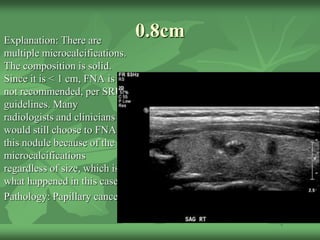

0.8cmExplanation: There are

multiple microcalcifications.

The composition is solid.

Since it is < 1 cm, FNA is

not recommended, per SRU

guidelines. Many

radiologists and clinicians

would still choose to FNA

this nodule because of the

microcalcifications

regardless of size, which is

what happened in this case.

Pathology: Papillary cancer!